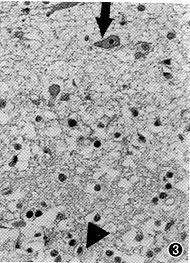

图3 老龄患者嗅球.突触小球的球形结构消失,突触小球层萎缩

导致外颗粒层外移,僧帽细胞(↑),内颗粒细胞层(▲) HE×400

2.老年患者嗅球改变的组织学特点:以青壮年组作对照,该组突触小球的数量为17~20个(群),僧帽细胞20~23个。老年患者的突触小球层和僧帽细胞层有明显改变者8例。突触小球减少为10~12个(群)者2例(分别为65岁及72岁),其形态变为中等大,僧帽细胞亦呈中度减少(9~14个);突触小球减少至4~8个(群)者2例(分别为60岁及85岁),其形态变为更小,僧帽细胞呈中度减少(9~14个);突触小球结构不清者4例(分别为63岁、83岁、85岁及87岁),其中僧帽细胞中度减少3例(9~13个),重度减少1例(5个);伴有突触小球内纤维状结构消失者2例,表现为呈云雾状均值的强嗜伊红块结;在老年患者嗅球的6层结构中,嗅神经纤维层、外颗粒层、内颗粒层及嗅束神经纤维层的形态无明显变化,而嗅球6层结构不清伴细胞总数明显减少1例(72岁),其僧帽细胞重度减少(5个)。此外,因突触小球层不同程度萎缩造成外颗粒层外移6例(图2,3);伴有小球周细胞体减少9例;出现明显淀粉样小体5例,其中3例为+++,2例为++;出现软脑膜钙化斑2例。